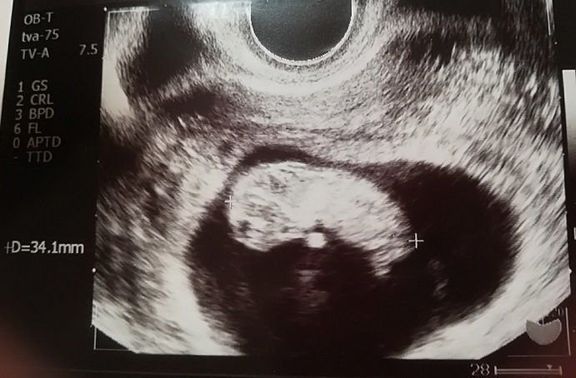

"おなかの中はどうなっていくの? エコー写真で振り返る、高齢ママのはじめての妊娠生活" -

待望の妊娠判明!エコー写真に見る、我が子を胸に抱くまでの“命の軌跡275日” -